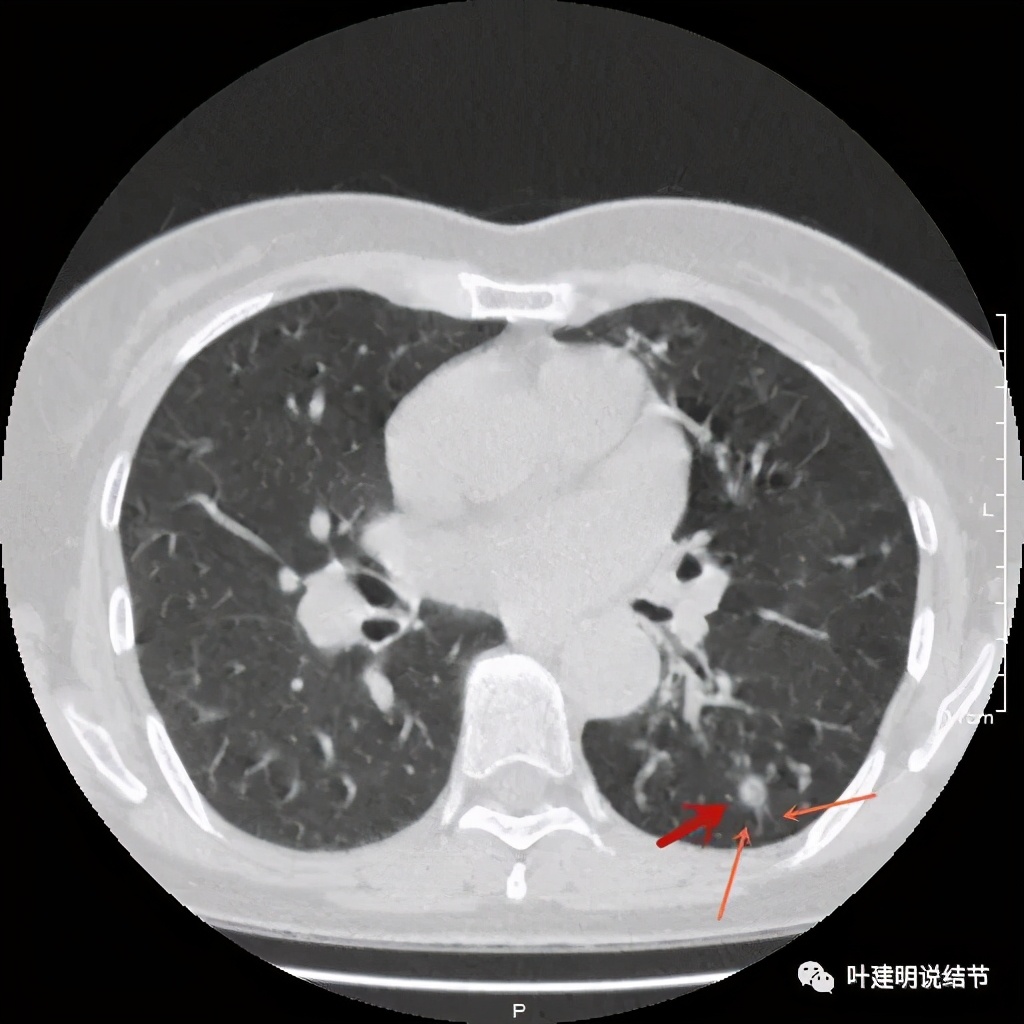

其实若从以上影像上看,恶性还真不能除外的,相对来说,恶性的可能应该大于良性。但看肺结节,我们在看细节特征的同时,还要看其他肺野有没有异常,综合来考虑。因为她的左下肺其他部位有病变存在,先来看下图像:

左下肺野多发支气管扩张呈囊状,也有一些实性密度的结节(考虑扩张支气管内的痰栓)。右侧也有实性炎性病灶。所以综合来看,左下之前的结节也得考虑与这些同源,一个原因来解释更为合理,所以恶性的可能性又小了。我建议其随访观察。昨天来复查,我们来看下这次的CT图像:

可见同样部位的左下结节已经较去年密度明显低了一些,说明有所吸收了!基本上已经只是磨玻璃密度了。那么其他病灶的情况呢?

也是有所变化,但病灶仍仍在,是异常的。最后这同图上还见到似乎也是实性伴小空腔的病灶(红色三角形标注处),是不是与之前的病灶有点像?